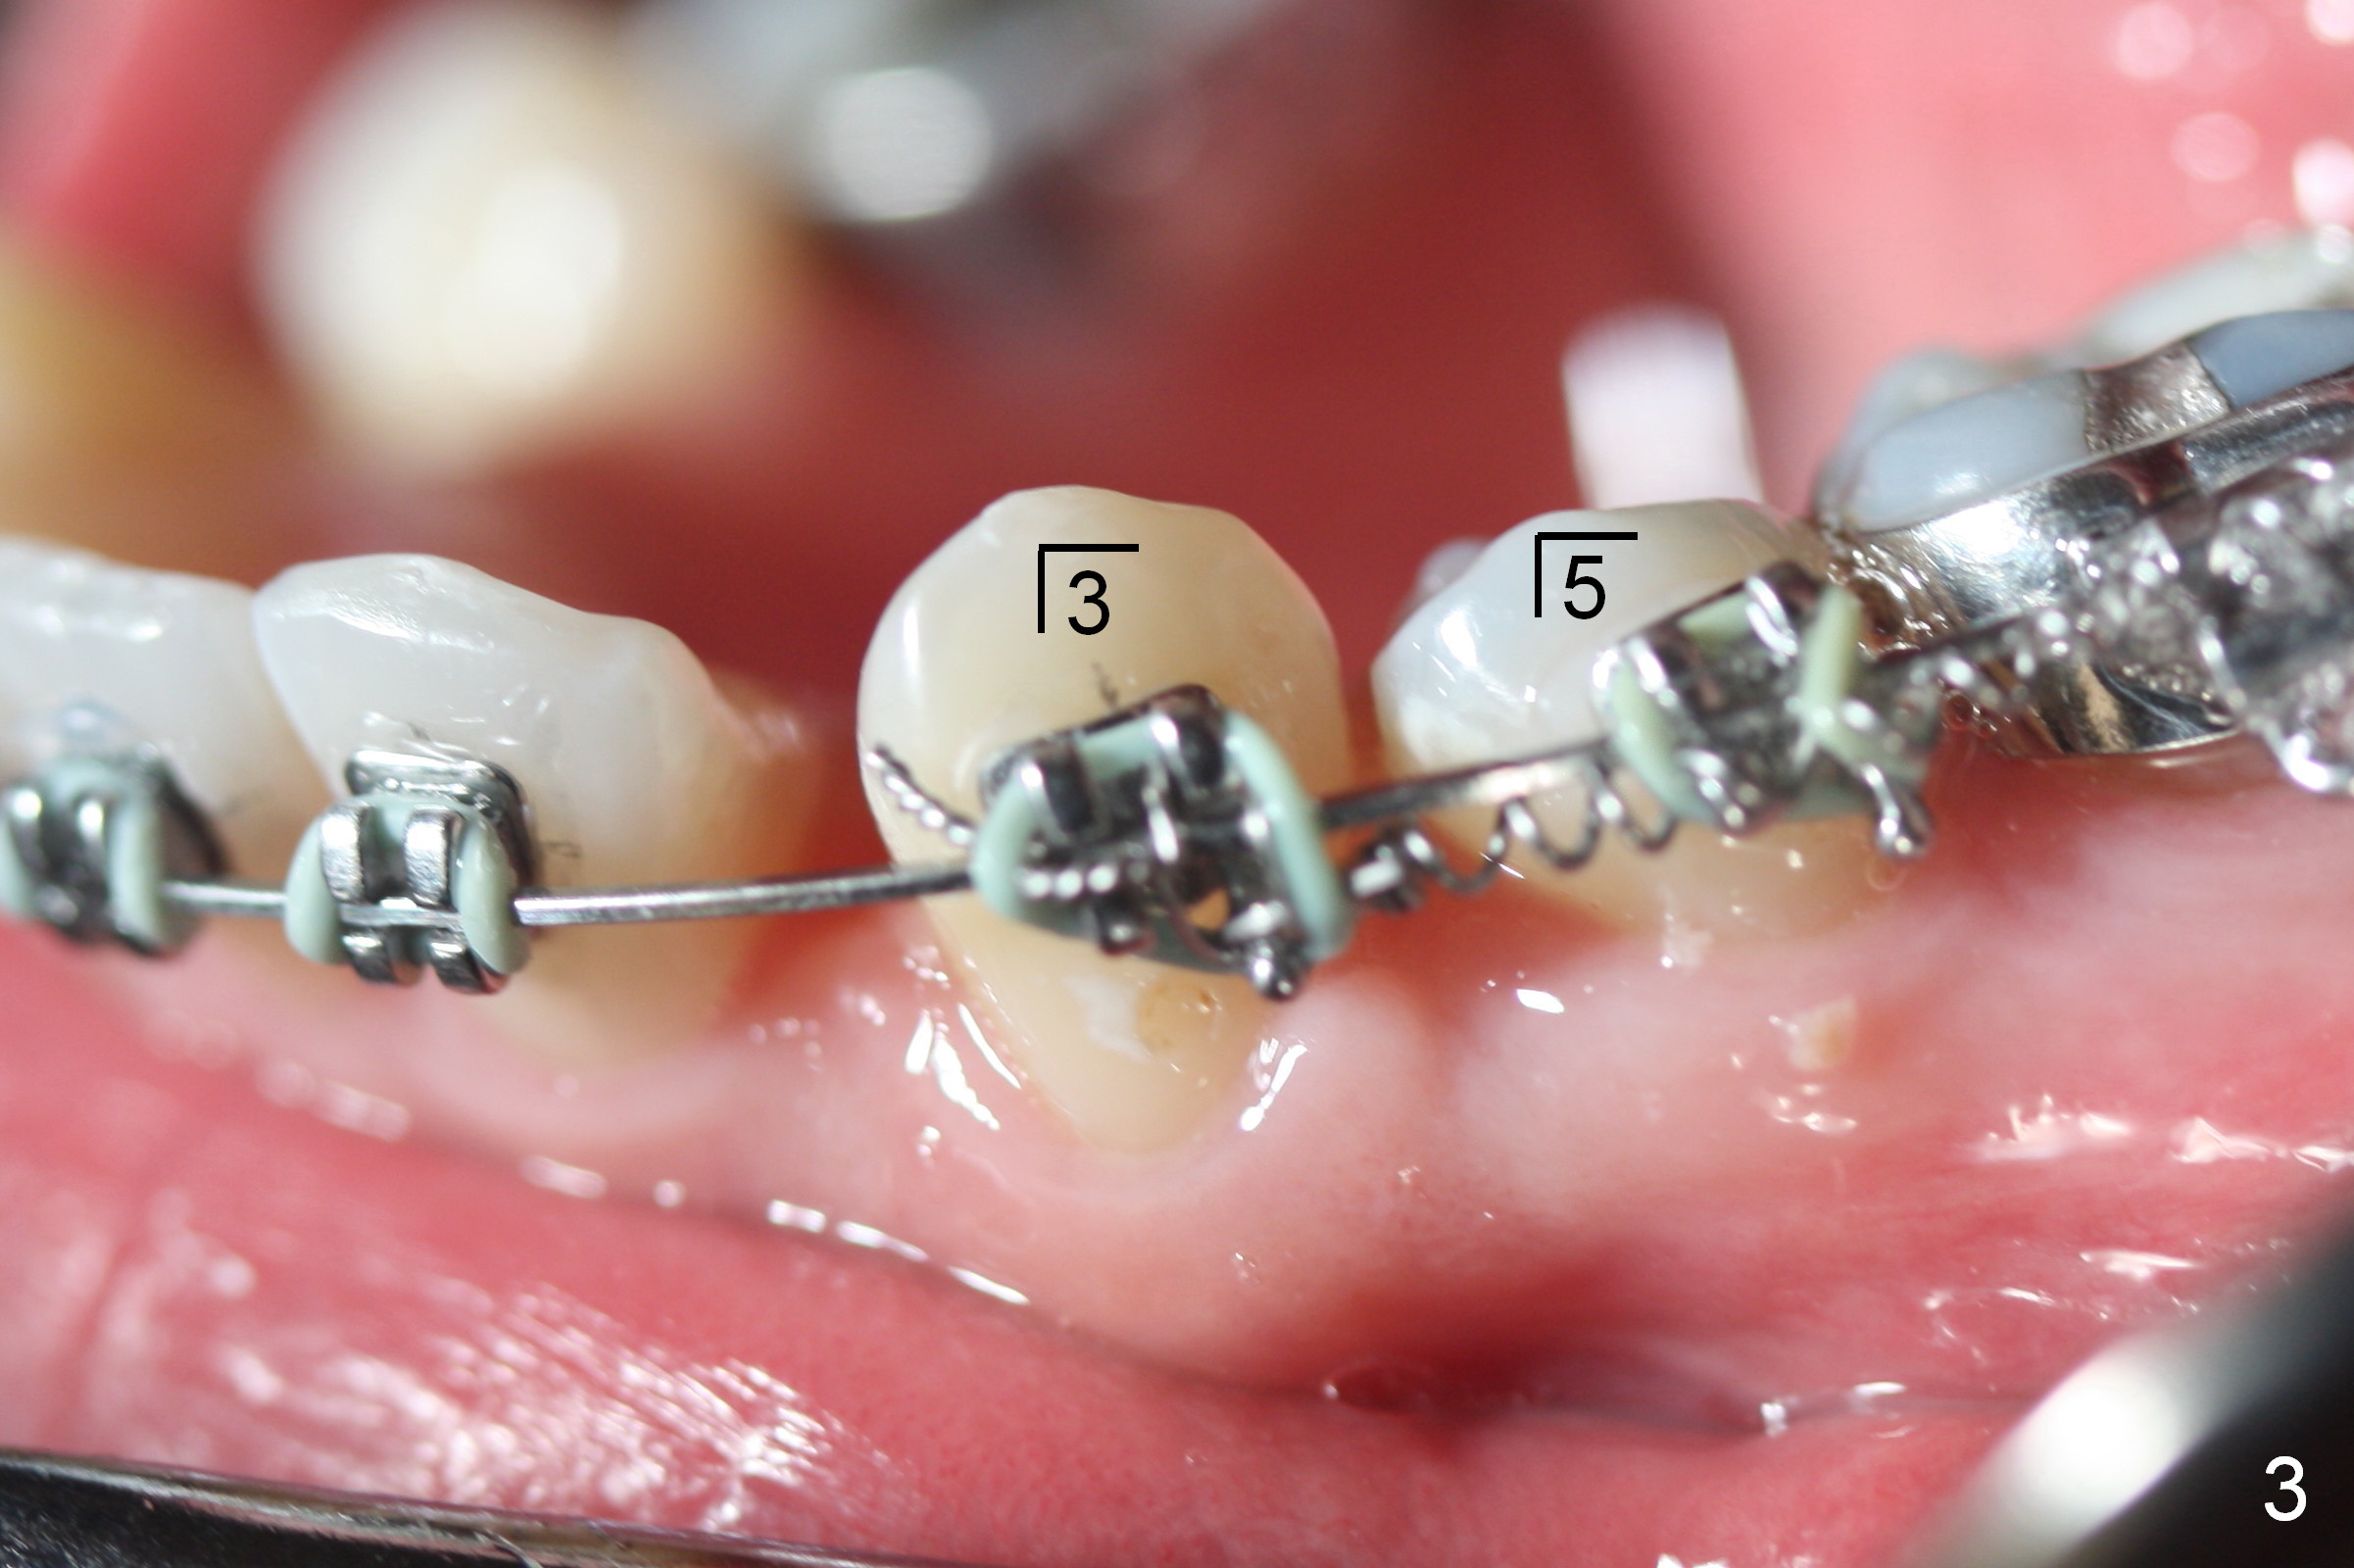

LR4 (Fig.1) and LL3 (Fig.2,3) are distalized 7.5 months of ortho treatment (1,2). Next step is to retract LR3 with closed coil spring (Fig.4) and de-rotate LL3 with a rotation wedge (Fig.5 *). The upper arch appears to be slightly in cross bite (Fig.4) 2 months after closed coil springs placed between the upper posted wire (<) and mini-implants (placed in the buccal tuberosity). Profile needs to be improved (Fig.6,7).

LR 3 shows no sign of distalization the 1st month after placed under closed coil spring (Fig.8), but obvious change occurs the 2nd months (Fig.9,10). Without closed coil spring, LL3 rotation (Fig.5) self corrects (Fig.8), but the tooth bounds back mesially. Closed coil spring is reloaded on LR3 9.5 months of treatment. If L3 are both distalized next visit (10.5th month), use a posted wire to distalize the lower incisors together.